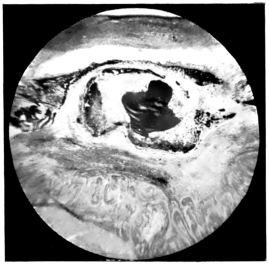

LENS DISLOCATED BETWEEN CILIARY BODY AND SCLERA

curly bracket span

11.